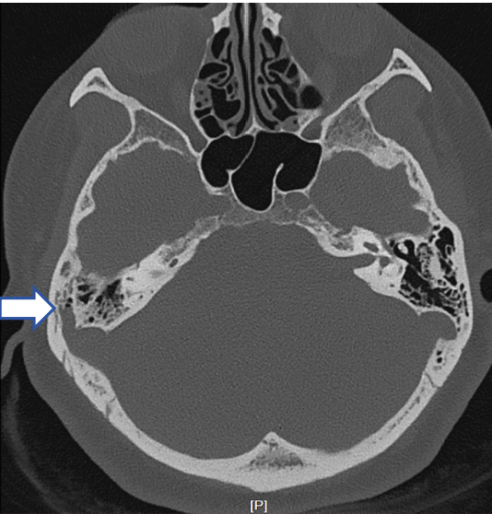

40岁的王女士,也是右耳搏动性耳鸣一年多,间断出现,与脉搏同步,后来逐渐加重,呈吹风样耳鸣声。双侧外耳道、鼓膜也没有异常,CT发现是右侧乙状窦骨壁缺损。

图片

初步诊断

血管性耳鸣,右侧乙状窦骨壁缺损